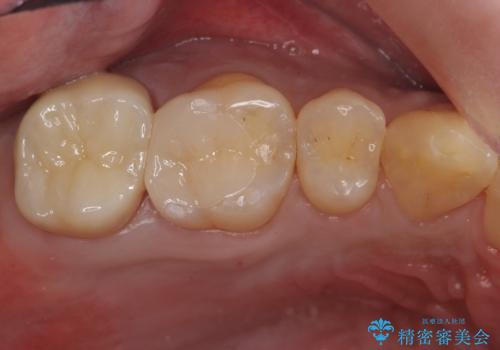

そのため、割れるリスクが少ない詰め物ではなく、被せ物による治療(ジルコニアクラウン)を行いました。

また、隣の歯も白い樹脂の下が虫歯になっており、セラミックの詰め物(e-maxインレー)による修復をしました。

白い被せ物が入り希望に沿った処置となり

大変満足して頂けました。